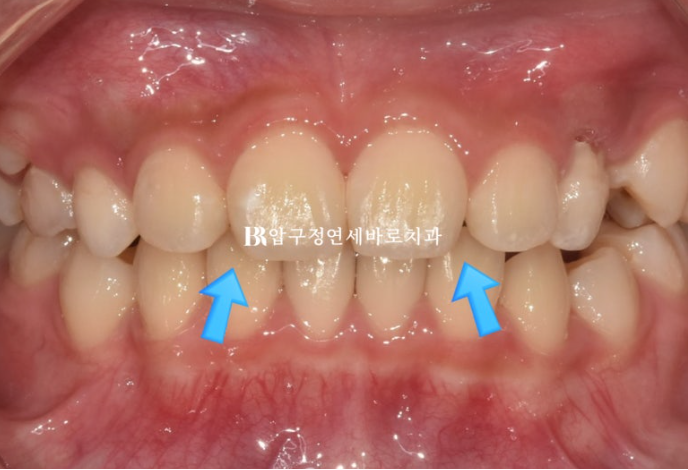

전 후 비교 사진 보겠습니다.

2022.09~2024.09

중심선은 잘 맞았고 앞니가 깊게 물리는 과개교합도 개선이 되었습니다.

파란 화살표 부분을 자세히 보시면 가운데 앞니 모양이 바뀐 것이 보입니다.

사진에서 보이듯 항아리 모양 치아는 앞니가 잘 배열이 된 후에도 여전히 끝단이 벌어져 보입니다.

이런 치아모양의 문제는 성인에서 무삭제 라미네이트로 해결이 가능하지만, 무삭제 라미네이트가 가능한 나이까지 아이의 커리어가 있고 그냥 두기는 아쉽습니다.

간단한 레진치료로 아이의 미소가 달라질 수 있습니다.